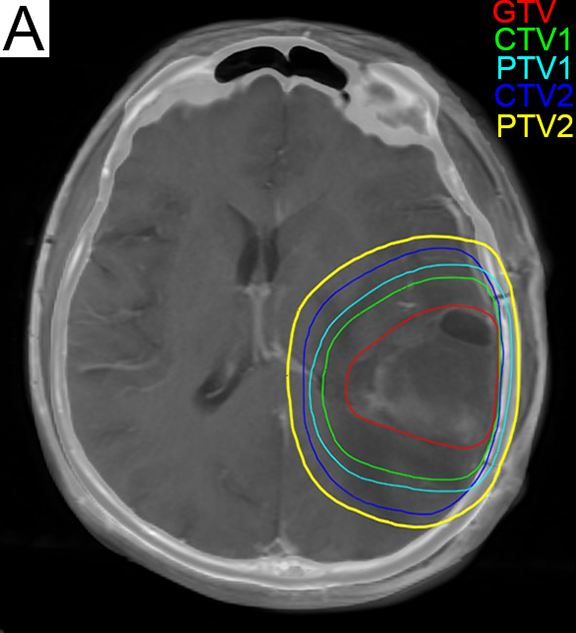

교모세포종은 종양세포의 강한 저항성, 정상 뇌조직 손상 가능성, 뇌의 제한적인 회복 능력, 약물의 뇌혈관장벽 통과 어려움 등으로 치료가 매우 어렵다.[66] 치료는 수술, 표준요법 항암방사선 동시치료(테모졸로마이드-방사선 복합치료), 표준요법 항암치료 순서로 진행되며, 환자 상태에 따라 추가적인 치료가 고려될 수 있다.1차 치료는 수술이며, 종양을 최대한 많이 제거하는 것이 효과적이다.[68] 글리올란(5-aminolevulinic aicd), 수술용 네비게이션 시스템 등을 사용하여 종양제거정도를 늘리고, 수술 중 모니터링이나 각성수술방법을 통해 환자의 신경학적 기능을 보존한다. 교모세포종은 뇌조직 침윤성이 높아 완전 제거 후에도 재발 가능성이 높아 항암치료와 방사선치료가 필요하다.[72]

수술 후에는 테모졸로미드(테모달) 병행 방사선 치료가 주요 치료법이다.[78] 1970년대 연구에 따르면 방사선 치료를 받은 환자의 중앙 생존 기간이 그렇지 않은 환자보다 두 배 이상 길었다.[79] 전뇌 방사선 치료보다는 3차원 입체 조형 방사선 치료가 효과적이며, 총 방사선량 60–65 Gy가 최적이다.[81]